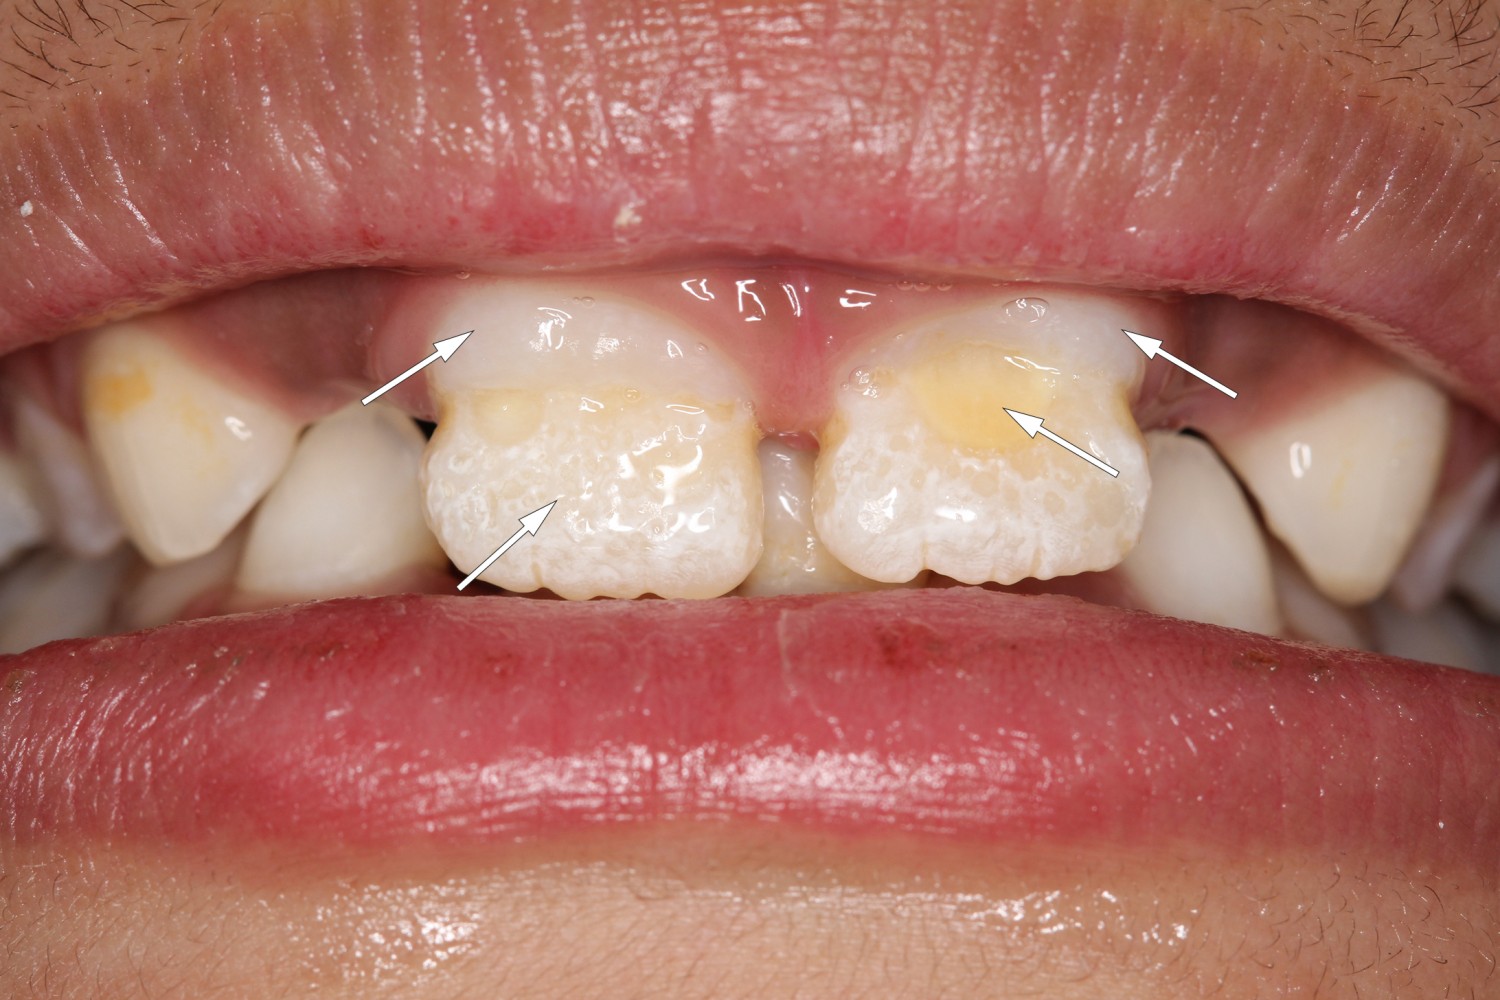

Forstyrrelser i kalsium- og fosfatstoffskiftet påvirker både ben- og tannutvikling (1). En tidligere frisk gutt ble henvist til spesialist i pedodonti fordi fortenner og seksårsjeksler hadde utviklingsskader. Fortennene var smale og tynne med hvite og gule flekker hvor emaljen stedvis manglet (se de to nederste pilene). Tilsvarende defekter kunne også ses på seksårsjekslene. Gutten ble ertet på skolen for stygge tenner. I tillegg til det rent estetiske var han plaget med ising i tennene. Melketennene var i hovedsak normale.

Mineralisering av permanente fortenner og seksårsjeksler starter rundt fødselen. Funnene hos denne gutten er forenlig med manglende kalsiumopptak på grunn av D-vitaminmangel frem til 18 måneders alder. Vi ser at emalje dannet etter at tilskudd ble gitt, har normal struktur (se de to øverste pilene), og rotutviklingen av de aktuelle tennene er helt normal. Røntgenbilder viser at også spissen på hjørnetennene er underutviklet. Disse starter mineraliseringen noen måneder senere, og skadene på hjørnetennene er dermed ikke forventet å være like omfattende. Skadene han har fått, vil medføre omfattende tannbehandling resten av livet, og det blir trolig behov for kronebehandling på mange tenner.